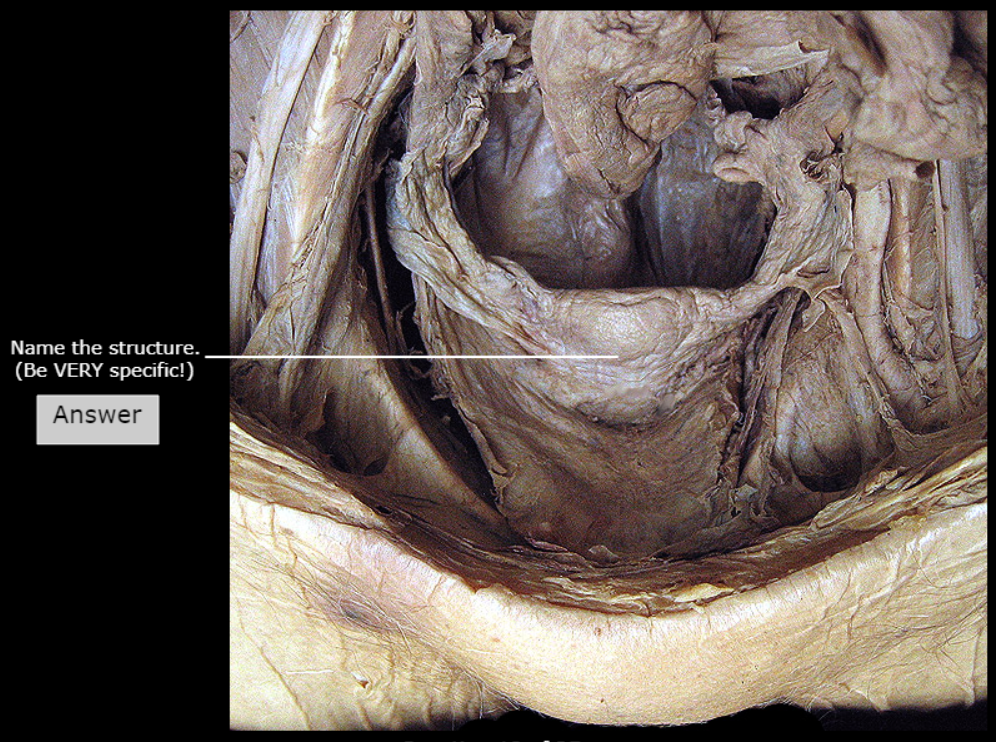

Prostate